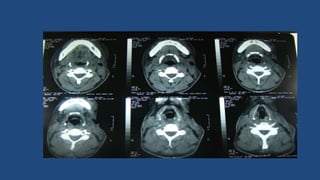

Mediastinite

• Processo infeccioso toma

uma via descendente no

pescoço, através dos

espaços látero-faríngeo,

retroferíngeo, alcançando a

bainha carotídea e chegam

ao tórax, na região do

mediastino

• Sinais e sintomas: dispnéia

intensa, dor torácica, febre

alta não-remissível

• Complicações: septicemia,

abscesso

mediastinal,empiema,efusã

o pleural, pericardite, óbito

(40% de mortalidade)

• Tratamento: além de

remoção da causa,

antibióticos e.v.,

traqueostomia, deve ser

feita a drenagem do tórax.

Mediastinite • Processo infecciosotoma uma via descendente no pescoço, através dos espaços látero-faríngeo, retroferíngeo, alcançando a bainha carotídea e chegam ao tórax, na região do mediastino • Sinais e sintomas: dispnéia intensa, dor torácica, febre alta não-remissível • Complicações: septicemia, abscesso mediastinal,empiema,efusã o pleural, pericardite, óbito (40% de mortalidade) • Tratamento: além de remoção da causa, antibióticos e.v., traqueostomia, deve ser feita a drenagem do tórax.